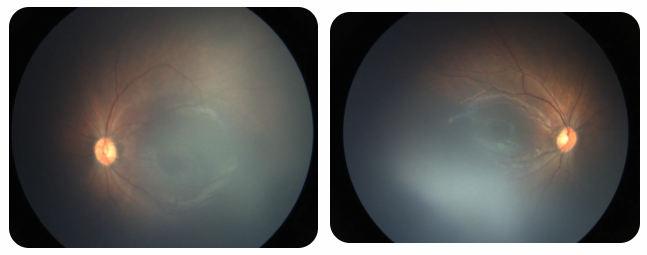

廈門眼科中心黎曉新名醫(yī)工作室曾接診一名31周出生的早產(chǎn)兒,出生體重僅1300克。由于家長缺乏篩查意識,直到孩子5個月大時眼睛仍不會追光,才前來就診。檢查發(fā)現(xiàn),患兒ROP已進展至4B期,因纖維血管增殖牽拉導(dǎo)致視網(wǎng)膜脫離,錯過了最佳治療窗口。盡管黎曉新教授團隊成功實施了玻璃體切割手術(shù),孩子的視力仍存在不可逆損傷。此后,孩子開啟了長期隨診復(fù)查、治療的“護眼征程”,目前其右眼矯正視力為0.6,左眼為0.8。

近期術(shù)前檢查:

早產(chǎn)兒視網(wǎng)膜病變

術(shù)后復(fù)查: